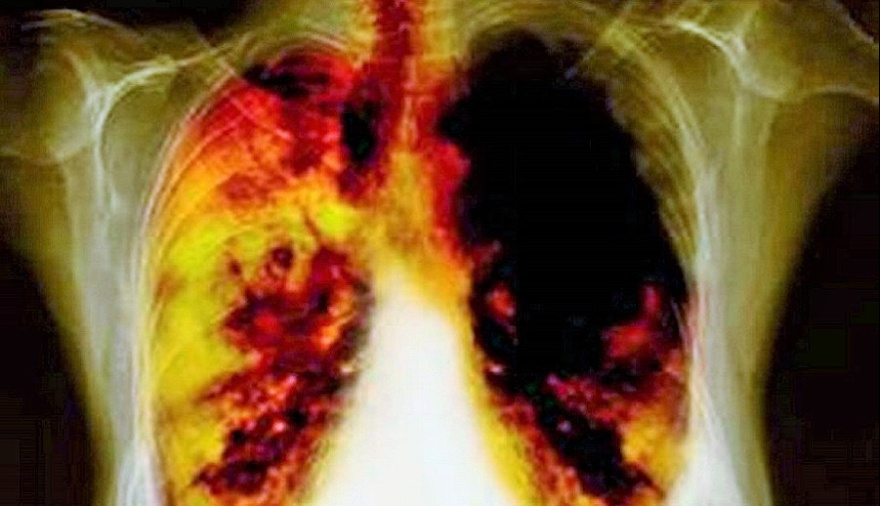

Más del 80% de las muertes por cáncer de pulmón están relacionadas con el tabaco, según datos de la publicación inaugural del Atlas del tabaco de EE.UU. de la Asociación Americana del Corazón (American Heart Association).

Eso es a pesar de que el tabaquismo entre los adultos se redujo de un 42 por ciento en 1965 a apenas un 11 por ciento en 2023, dijeron los investigadores.